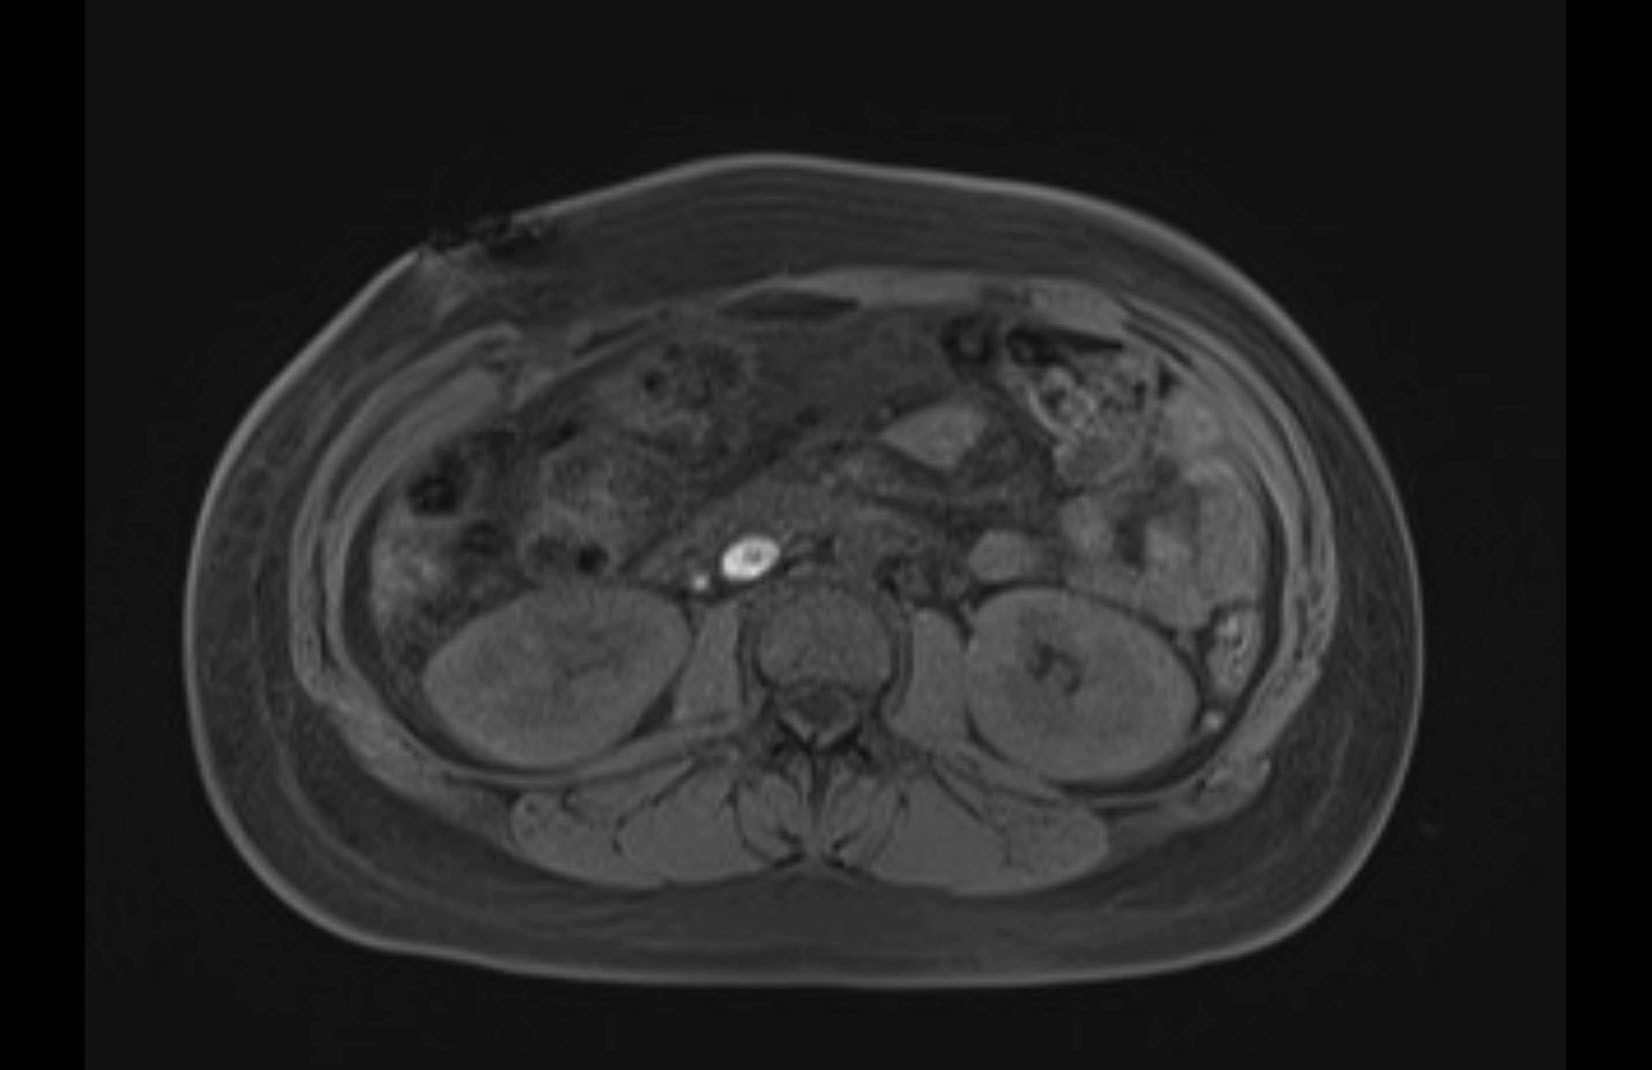

MRI T1

MRI T2

Imaging analysis

Based on initial findings, which issue(s) would you be most concerned about?